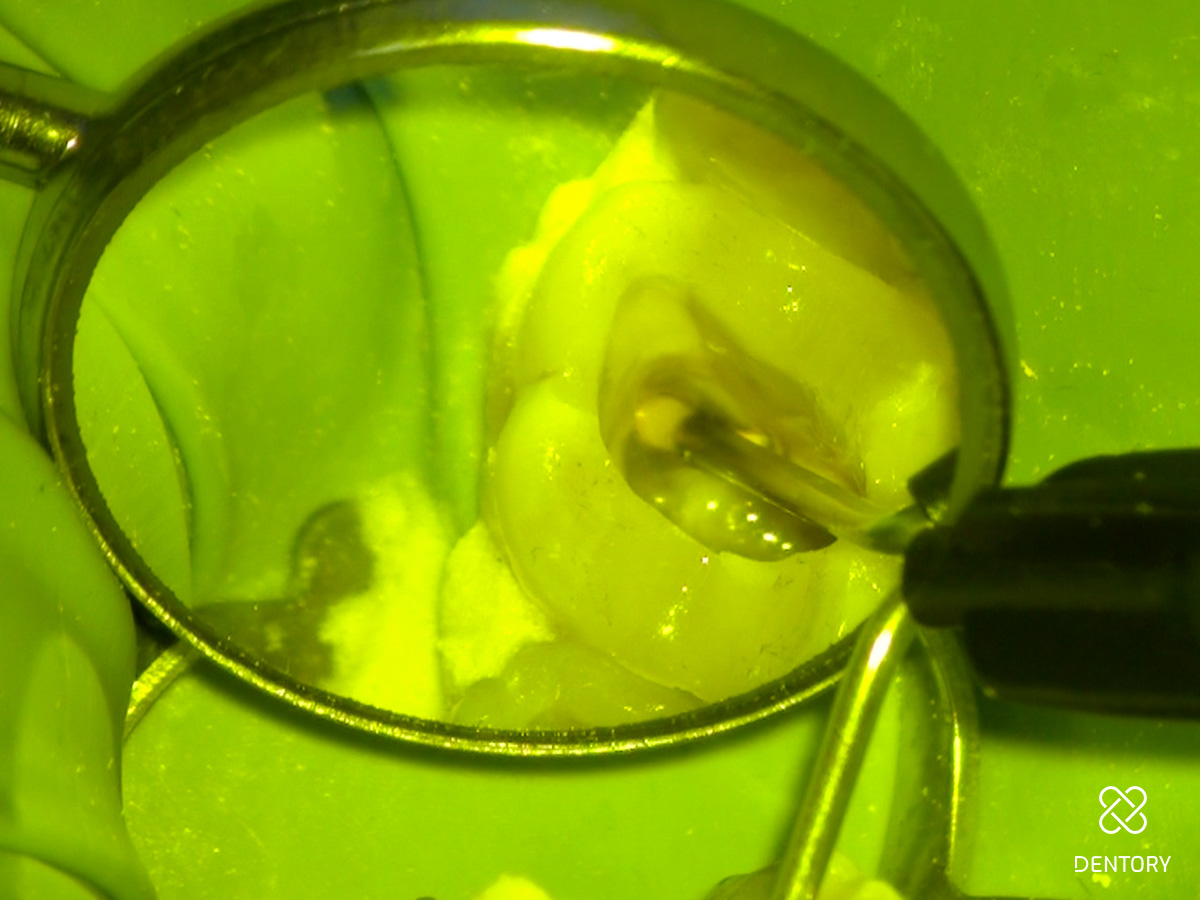

Abbildung 1

Klinische Ausgangssituation.